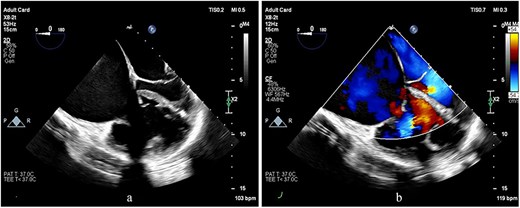

Preoperative transesophageal echocardiography (TEE) demonstrated marked RV and RA enlargement, severe RV systolic dysfunction, thickened RV walls, severe TR due to annular dilation, and severe PV stenosis. No ventricular septal defect was observed preoperatively (Figs 1–3). The left ventricle (LV) appeared small and D-shaped, consistent with elevated RV pressures (Table 1).

TEE images at the mid-esophageal level, four-chamber view, obtained with clockwise rotation focusing on the right heart. (a, b) The images demonstrate severe RV and RA enlargement, dilated tricuspid annulus, and functional TR. Note the leftward shifting of the interatrial septum toward the LA cavity, consistent with elevated RA pressure.